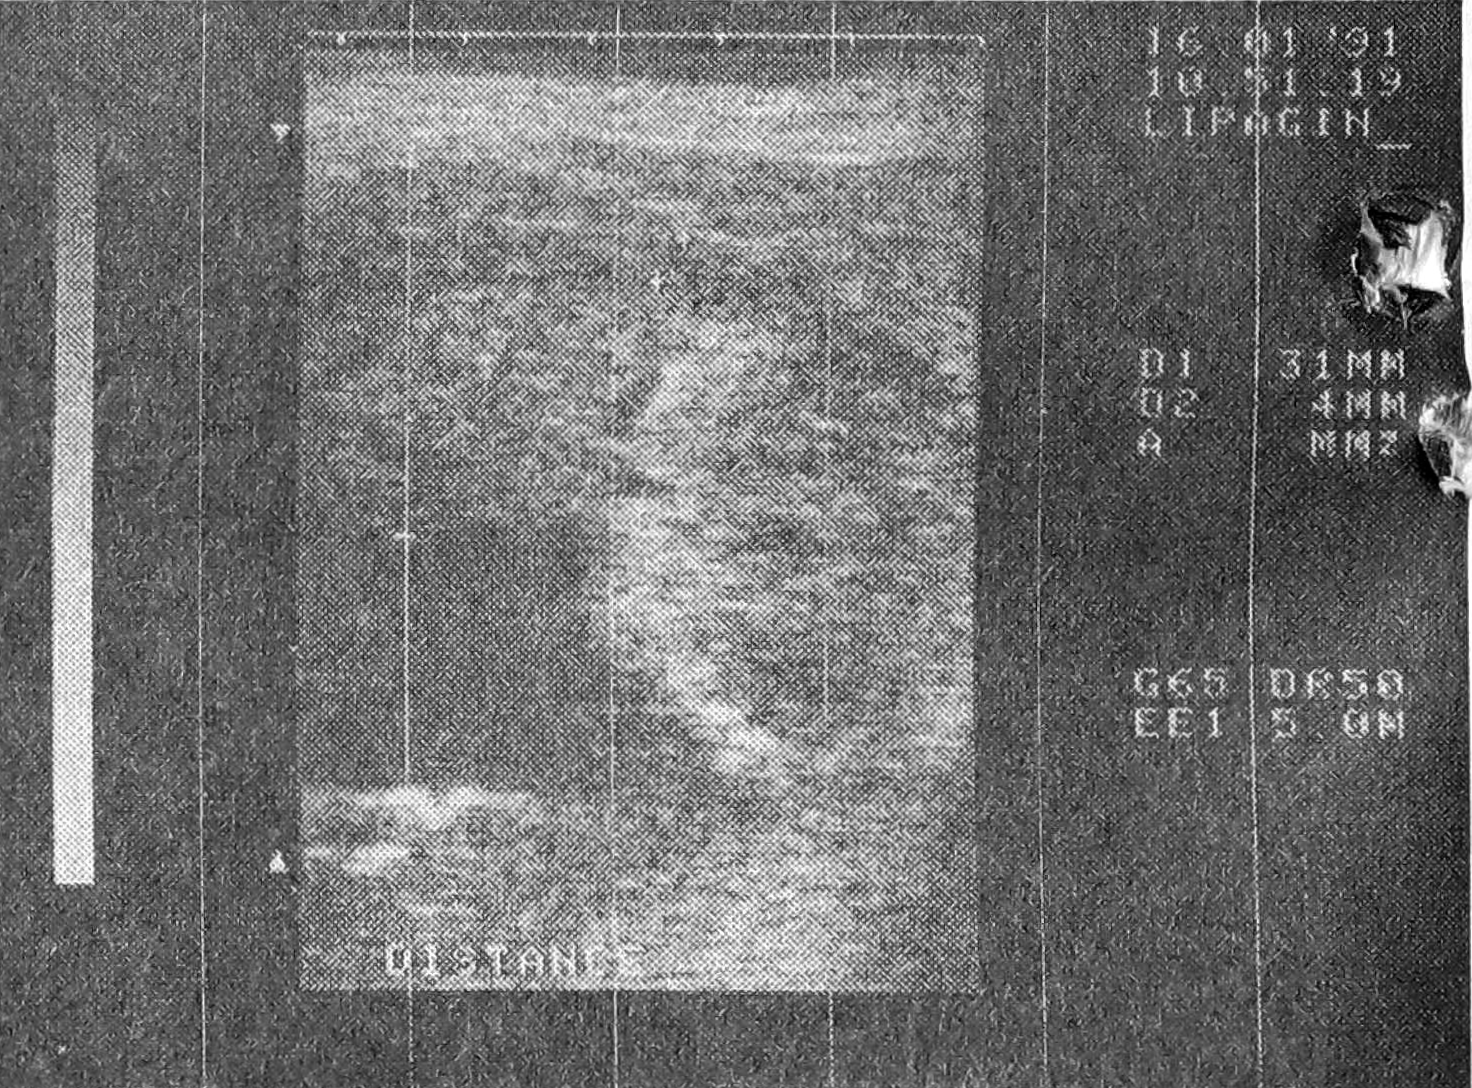

При инвазии опухоли в соседние органы возникает проблема дифференциальной позволяет определить принадлежность опухоли, уточнить локализацию и стадию новообразования даже при недостаточной емкости мочевого пузыря [1, 2]. При использовании линейного трансректального датчика (“Тошиба” — SAZ 35А, 5 мГц) по сравнению с ротационным (“Брюль и Къер” 1846, 5 мГц) сонографическая картина представляет собой сагиттальное изображение не только шейки мочевого пузыря, но и предстательной железы, семенных пузырьков и окружающих тканей (рис. 1). Однако не всегда при инвазивных формах рака представляется возможным точно определить границу и первичный опухолевый компонент только на основании диагностики новообразований предстательной железы и мочевого пузыря при локализации последнего в области шейки [6]. Трансректальное ультразвуковое сканирование в таких случаях эхографических признаков. Солидные формы рака мочевого пузыря с выраженным эндофитным ростом, прорастающие в предстательную железу широким фронтом, имеют на ультрасонограммах гипоэхогенную или смешанную эхоструктуру, приближаясь по характеру к эхоструктуре предстательной железы (рис. 2), и трудно поддаются дифференцировке. Интимный анатомический контакт шейки мочевого пузыря и краниального отдела предстательной железы, как правило, не позволяет дифференцировать рак мочевого пузыря в стадии Т3а и таковой в стадии Т3б что еще более затрудняет выбор лечебной тактики.

Рис. 2. Трансректальная линейная ультразвуковая сонограмма мочевого пузыря. Определяется рак мочевого пузыря с прорастанием в предстательную железу.